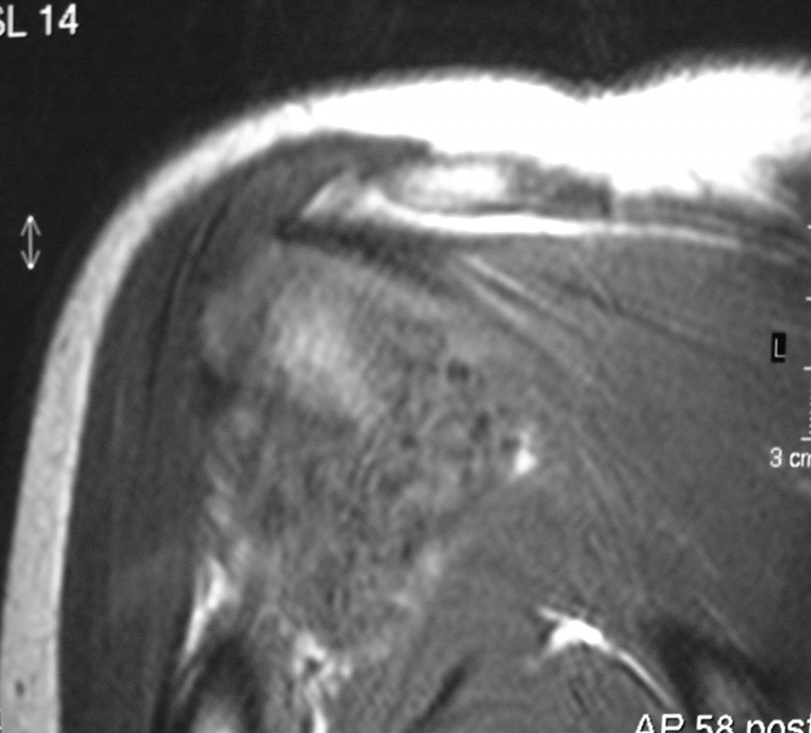

Synovial chondromatosis is an uncommon, benign, process that occurs in large joints, such as the knee (50%), hip, elbow, or shoulder. This process mainly affects synovium and hence most commonly arises from joints and tendons which are lined by synovium. Synovial Chondromatosis may also affect bursae and extend into surrounding soft tissues. This condition is seen in patients between 20 and 50 years of age and most commonly in men (male-female ratio of 2-4/1). The patient usually complains of pain, stiffness, crepitance, swelling, and joint locking. The knee is the most common site to be affected. Symptoms are long-standing and progressive. The plain x-ray may be normal (5 to 33%) or there may be small flecks of calcification (Fig. 1 & 2). On MRI the nodules of cartilage are easily seen. MR imaging may also show synovial thickening, joint erosions and intraarticular calcifications. The signal characteristics of these intraarticular bodies depend of their composition. If mineralization is not present the signal intensity follows the cartilage signal with intermediate signal on T1 images and high signal on T2 weighted MR images. Uniformly calcified bodies follows bone density on all sequences with bone marrow signal centrally and low signal peripherally (Fig. 3-5). Histologically the cartilage is arranged in nodules, which are quite cellular (Fig. 7-9). Synovial lining is present surrounding the cartilage nodules (Fig. 8). The cartilage nodules are often referred to as loose bodies however they are not really loose and embedded in the synovium lining. This is considered a metaplastic condition as opposed to a true neoplastic condition. Rarely it may turn into a malignancy usually a low grade chondrosarcoma. Malignant change is suggested by deep erosions into adjacent bone.

Fig. 4 & 5. MR images of the right shoulder. Axial (Fig. 4) and coronal (Fig. 5) T2-weighted images demonstrate high signal in the right shoulder corresponding with proliferation and swelling of the synovium. Multiple bodies with low signal that follow bone density in all sequences.